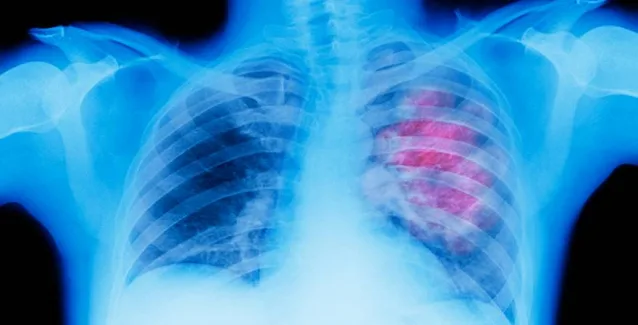

Ο καρκίνος του πνεύμονα είναι η πρώτη αιτία θανάτου από καρκίνο σε άνδρες και γυναίκες. Αυτό, όμως, δεν συνέβαινε πάντα. Σήμερα, το κάπνισμα προκαλεί περίπου εννέα στους 10 θανάτους από καρκίνο του πνεύμονα, ενώ η ρύπανση και άλλα χημικά παίζουν μικρότερο ρόλο.

Ποια είναι τα συμπτώματα του καρκίνου του πνεύμονα;

Συνήθως δεν υπάρχουν συμπτώματα ή προειδοποιητικά σημάδια στα πρώτα στάδια. Καθώς εξελίσσεται, όμως, ο καρκίνος τα συμπτώματα είναι συνήθως μη ειδικά και μπορεί να περιλαμβάνουν: βήχα που δεν υποχωρεί, πόνο στο στήθος- ειδικά κατά τη βαθιά αναπνοή, συριγμό ή δυσκολία στην αναπνοή, βήχα με φλέγμα και αίμα, καθώς επίσης και κούραση.